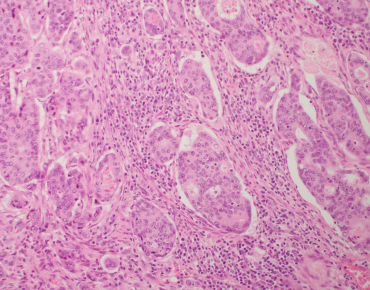

Over the past few years, Roberto Salgado, Sherene Loi and Carsten Denkert have developed the International Immuno-Oncology Biomarker Working Group on Breast Cancer, with members including expert clinical research groups, pathologists, clinicians and statisticians worldwide currently knowledgeable in the field of Immune-oncology Biomarkers. The purpose of this Working Group is to develop, in a timely manner, standards on the assessment of Immuno-Oncology Biomarkers to aid pathologists, clinicians and researchers in their research and daily practice.

All materials on this website, including images, annotations, and similar research and educational data, are anonymized and are therefore freely available to browse, download, and use for scientific and educational purposes.